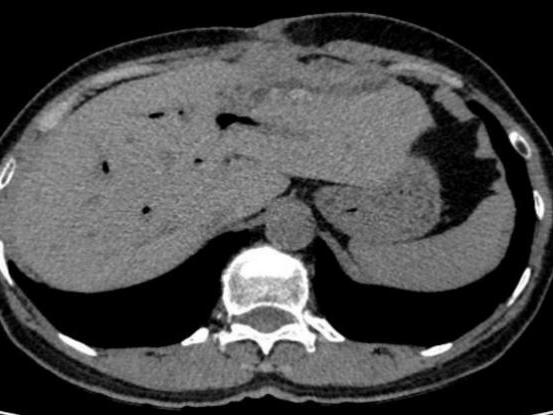

结果检查一看:患者肝内胆管存在多发结石并伴有胆管扩张。由于结石长期在体内“作祟”,引发了局部组织的严重炎症和破溃,最终导致肝脏穿孔,并与腹壁形成了一条异常的“窦道”(瘘管)。这条通道使得肝脏内的感染物直接穿出腹壁,造成了腹壁流脓的危重局面。

棘手的是,患者既往有多次腹部大手术史,腹腔解剖结构早已发生改变,加之合并2型糖尿病,术前营养状况极差。而且局部病变性质不明,高度怀疑存在恶变可能。

张继红教授带领手术团队沉着应对、精准操作,小心翼翼地层层分离粘连组织,逐步梳理紊乱的解剖结构,最终发现肝左叶与腹壁之间形成了约1cm宽的致密瘘管,管内可见少量白色分泌物,正是这处“漏点”导致患者腹壁反复流脓。在精准保护周围肠管、重要血管不受损伤的前提下,团队成功切除病变的左半肝,彻底清除病灶。

术后解剖离体肝脏标本发现,患者肝内胆管扩张明显,内有多发褐色结石,最大直径达1×1cm,这些结石长期反复刺激胆管壁,正是引发肝脏穿孔、腹壁流脓的根本原因。